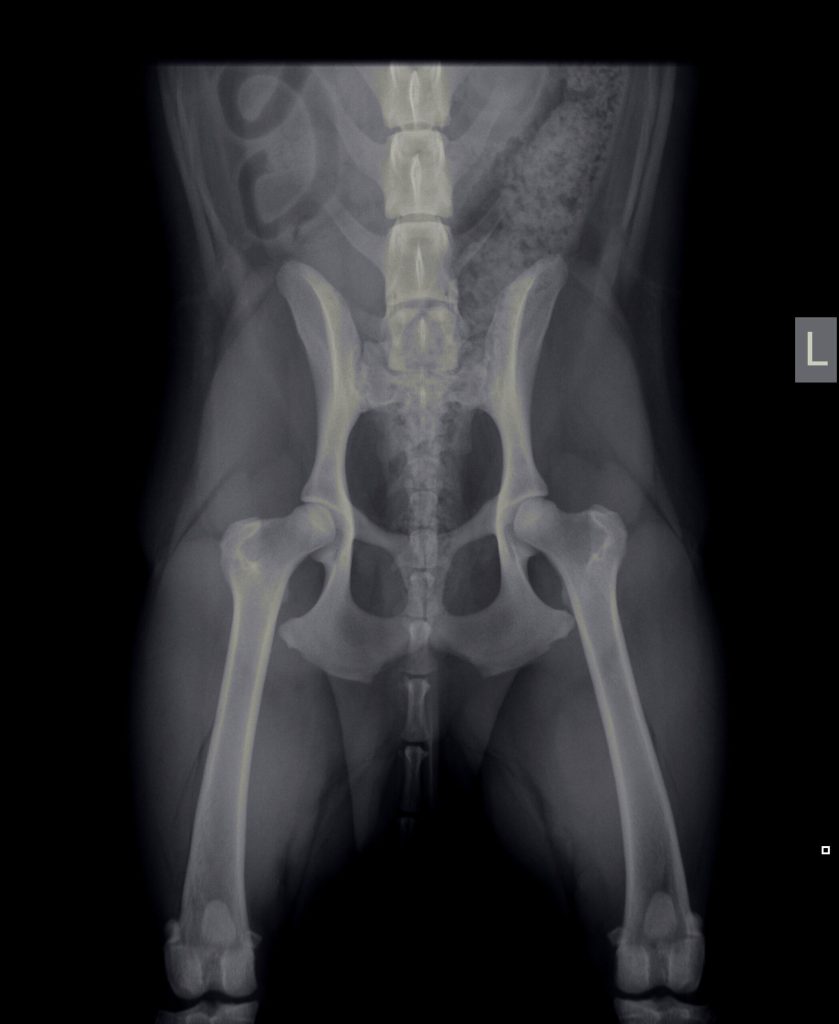

Diagnostiek

Het stellen van een diagnose kan soms net spoorzoeken zijn. Soms is het eenvoudig en soms is het lastig.

Onze diagnostische mogelijkheden hebben we uitgebreid door de aanschaf van vele soorten van apparatuur en het volgen van allerlei cursussen.